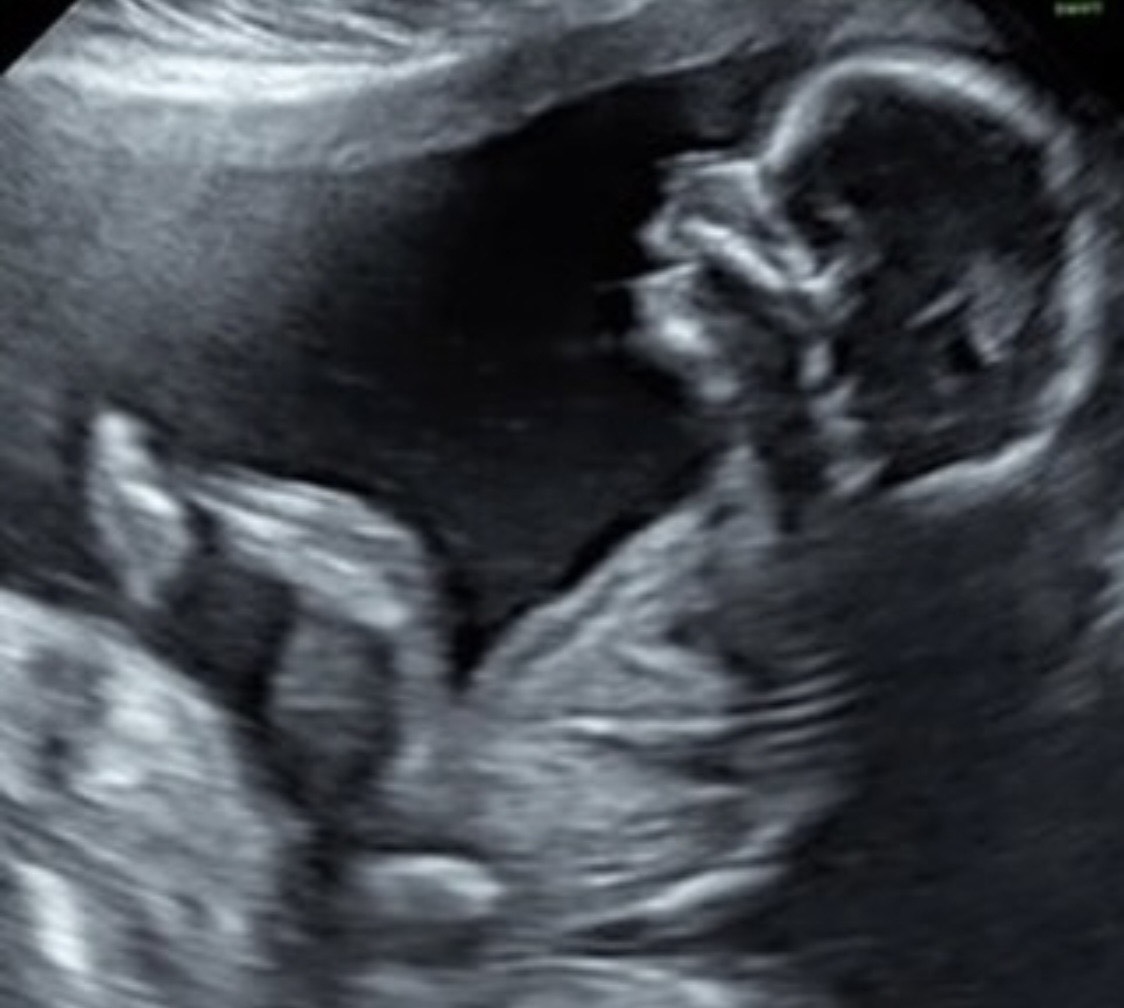

Loppuraskauden ultraääni on nimensä mukaan ajateltu raskauden viimeisille viikoille (noin rv 36+0 alkaen) synnytystapa-arvion tuntumaan. Tutkimuksen aikana mitataan vauvan strategiset mitat painoarviota varten, kuunnellaan sikiön sydänäänet ja nähdään missä asennossa hän kohdussa majailee. Tietysti myös sukupuolta voidaan tässäkin kohtaa arvailla, jos vauva on sen aikaisemmin piilottanut. Varsinkin loppuraskaudessa painoarvio on nimensä mukaisesti arvio ja siinä on helposti 10% virhemarginaali eli 3,5kiloisella vauvalla 350gr. Siksi arvioimme vauvan kokoa myös kokeilemalla vauvan kokoa vatsan päältä käsin. Tässä vaiheessa lapsivettä on useimmiten niukasti ja vauva alkaa olla matalalla lantiossa eikä välttämättä kuvaa saada kuin korvalehdestä tai kyynärpäästä.

Vastaanotolla voidaan halutessasi tutkia myös kohdunsuun tilanne, jos raskaus on täysiaikainen eli rv 38+0. Muistathan, että kohdunsuun tutkimisella ei voi ennustaa synnytyksen käynnistymistä suuntaan eikä toiseen, se on vain tämän hetken tilanne.